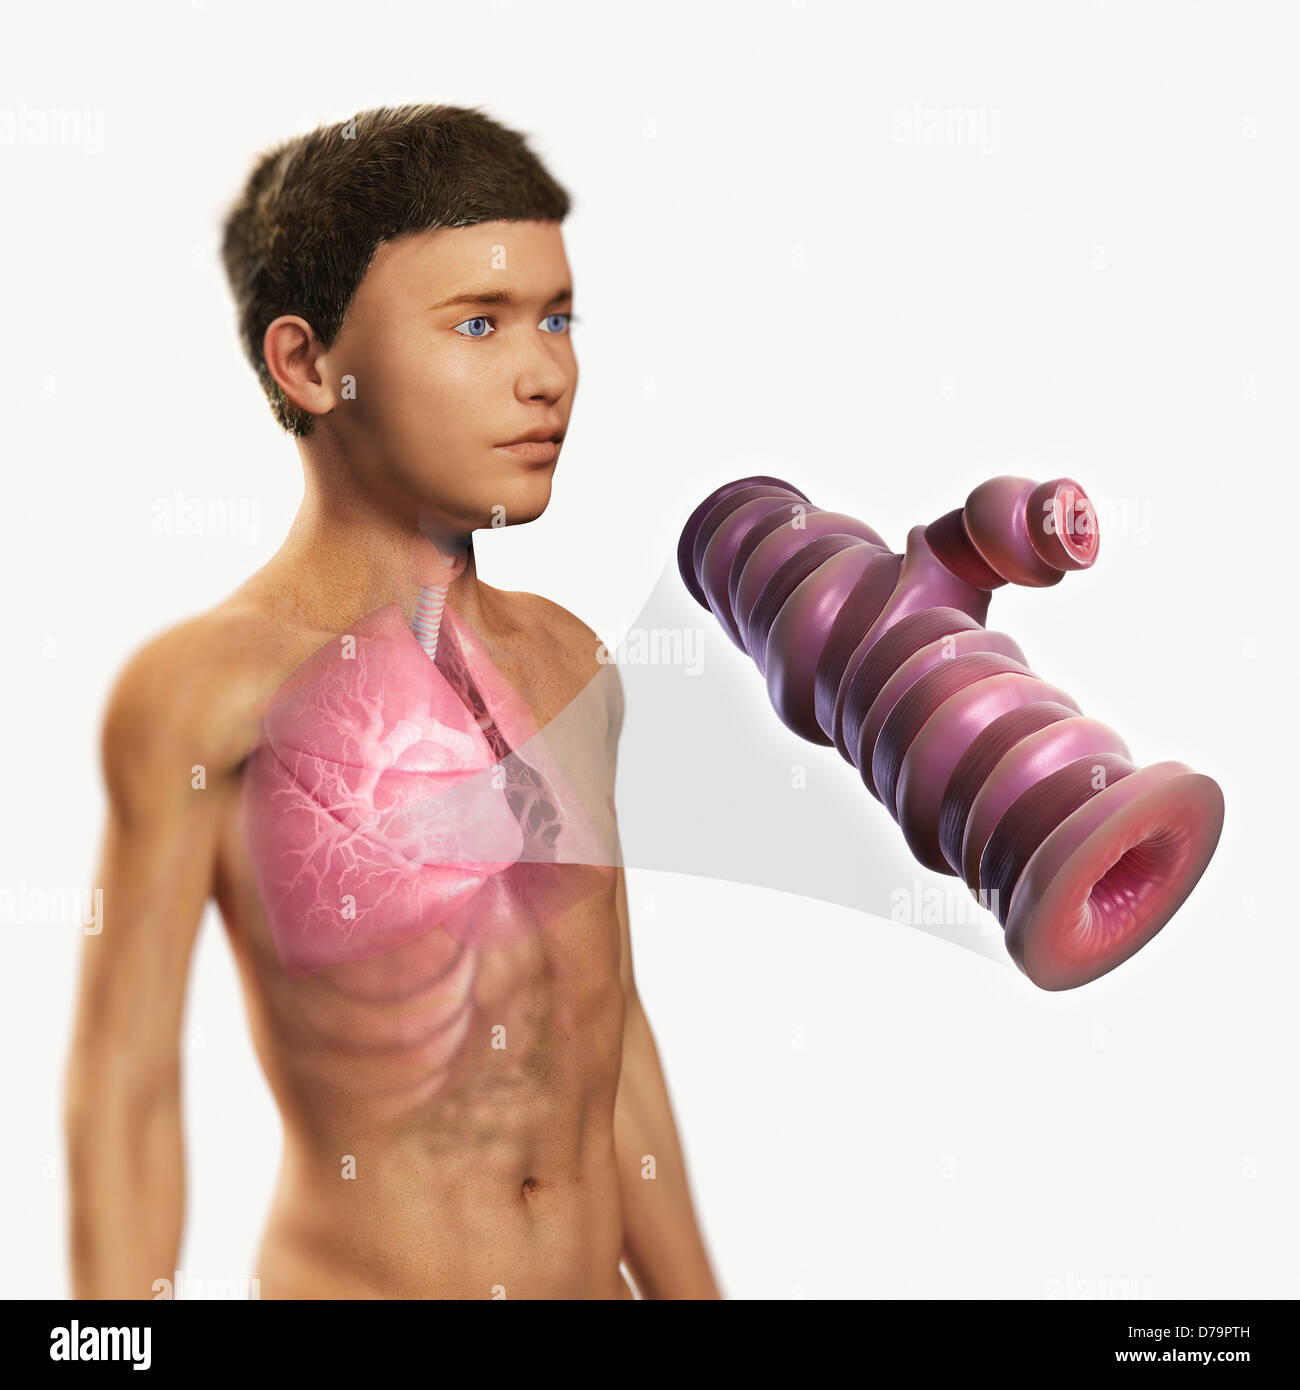

Asthmatic Airway Stock Photohttps://www.alamy.com/image-license-details/?v=1https://www.alamy.com/stock-photo-asthmatic-airway-56149201.html

Asthmatic Airway Stock Photohttps://www.alamy.com/image-license-details/?v=1https://www.alamy.com/stock-photo-asthmatic-airway-56149201.htmlRMD79PTH–Asthmatic Airway

Asthmatic Airway Stock Photohttps://www.alamy.com/image-license-details/?v=1https://www.alamy.com/stock-photo-asthmatic-airway-56149109.html

Asthmatic Airway Stock Photohttps://www.alamy.com/image-license-details/?v=1https://www.alamy.com/stock-photo-asthmatic-airway-56149109.htmlRMD79PN9–Asthmatic Airway

Asthmatic Airway Stock Photohttps://www.alamy.com/image-license-details/?v=1https://www.alamy.com/stock-photo-asthmatic-airway-56149136.html

Asthmatic Airway Stock Photohttps://www.alamy.com/image-license-details/?v=1https://www.alamy.com/stock-photo-asthmatic-airway-56149136.htmlRMD79PP8–Asthmatic Airway

Asthmatic Airway Stock Photohttps://www.alamy.com/image-license-details/?v=1https://www.alamy.com/stock-photo-asthmatic-airway-56149371.html

Asthmatic Airway Stock Photohttps://www.alamy.com/image-license-details/?v=1https://www.alamy.com/stock-photo-asthmatic-airway-56149371.htmlRMD79R2K–Asthmatic Airway